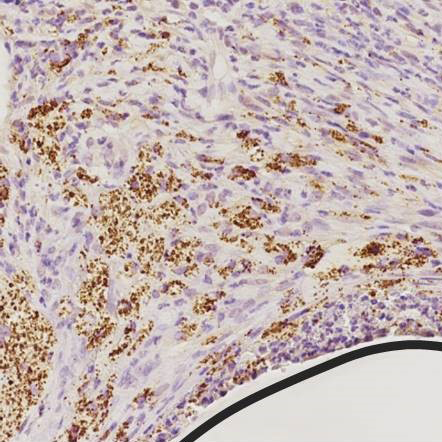

In our chemical and radiochemical laboratories, we develop new tracers for diagnostic molecular imaging using positron emission tomography (PET), single-photon emission tomography (SPECT), optical and photoacoustic imaging. On the one hand, we focus on specific ligands for the alarmins S100A8/S100A9; on the other hand, we work on bacteria-specific tracers based on complex carbohydrates or siderophores. Various short-lived nuclides such as the positron emitter fluorine-18 or the gamma emitter technetium-99m are used. In our workgroup we also develop absorbers for improved photoacoustic imaging.